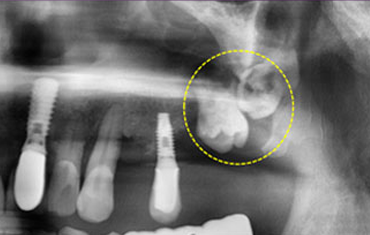

윗턱뼈에 사랑니가 매복된 경우

윗턱뼈 공기주머니에 뼈이식

치료 전

치료 후